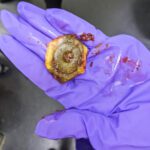

Over the next week, the dog continued to vomit intermittently, had a decreased appetite and weight loss, and produced only small amounts of stool. His blood test results were all normal. Repeat x-rays were still unimpressive as far as gas distention of his bowel, but the offending foreign body could finally be seen. At surgery, a hard plastic hexagon-shaped object was removed from the small intestine where it was lodged. The hole in the center of the object allowed the contents of the intestines to pass through, thereby preventing a more easily diagnosed full blockage. He should experience a full and smooth recovery.